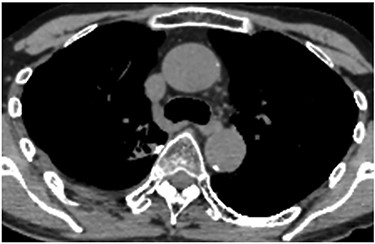

A 60-year-old man underwent right apical and posterior segmentectomies via VATS for early-stage lung cancer. The bronchus and pulmonary parenchyma were divided by endoscopic staples (Echelon®; Ethicon Endo-Surgery). The resected tumour was 1.5 cm in the longest diameter and pathologically diagnosed as Stage IA adenocarcinoma. The patient was discharged uneventfully on eighth day after surgery. Chest radiography revealed no significant findings, and laboratory data were within the normal ranges on the 14th day after discharge at a scheduled visit to the outpatient clinic. However, the patient was transported by ambulance to our hospital owing to a sudden onset of chest pain and dyspnoea on the 32nd day after discharge. He developed hypotension and tachycardia with systolic blood pressure of 50 mmHg and heart rate of 114 beats/min. The haemoglobin concentration level, which had been 12.3 mg/dl on the 14th day after discharge, decreased by 8.7 mg/dl. Chest radiography revealed a massive right pleural fluid, and enhanced computed tomography (CT) showed an extravasation of contrast media near the fifth thoracic vertebra (Fig. 1). The patient was diagnosed with haemothorax and an emergency operation was performed. Thoracoscopic examination revealed massive blood coagulation in the right thoracic cavity, with no adhesions. After removal of the coagulation, continuous active bleeding from the intercostal artery was found near the fifth thoracic vertebra in the vicinity of a stump of the bronchus divided by a staple (Supplementary Video 1). A thoracotomy through the fifth intercostal space was therefore performed to achieve haemostasis, and the bleeding was stopped by suturing using a 4–0 nonabsorbable monofilament ligature. In addition, the bleeding point was covered with a collagen-fibrin patch (Tachosil®). The posterior part of the staple line of the lung parenchyma adjacent to the bleeding point under full inflation was partly exposed, whereas the bronchial stump was covered with lung. Therefore, the scratching created by the staples was assumed to cause haemothorax. The total amount of haematoma in the right thoracic cavity and the intraoperative blood loss was 3980 g. Postoperative CT confirmed that the stapler dividing the lung parenchyma directly faced the bleeding point beside the fifth vertebra (Fig. 2). The patient progressed satisfactorily after the reoperation and was discharged on ninth day after reoperation.

Postoperative CT revealing that the stapler dividing the lung parenchyma directly touched the fifth vertebra (arrow).